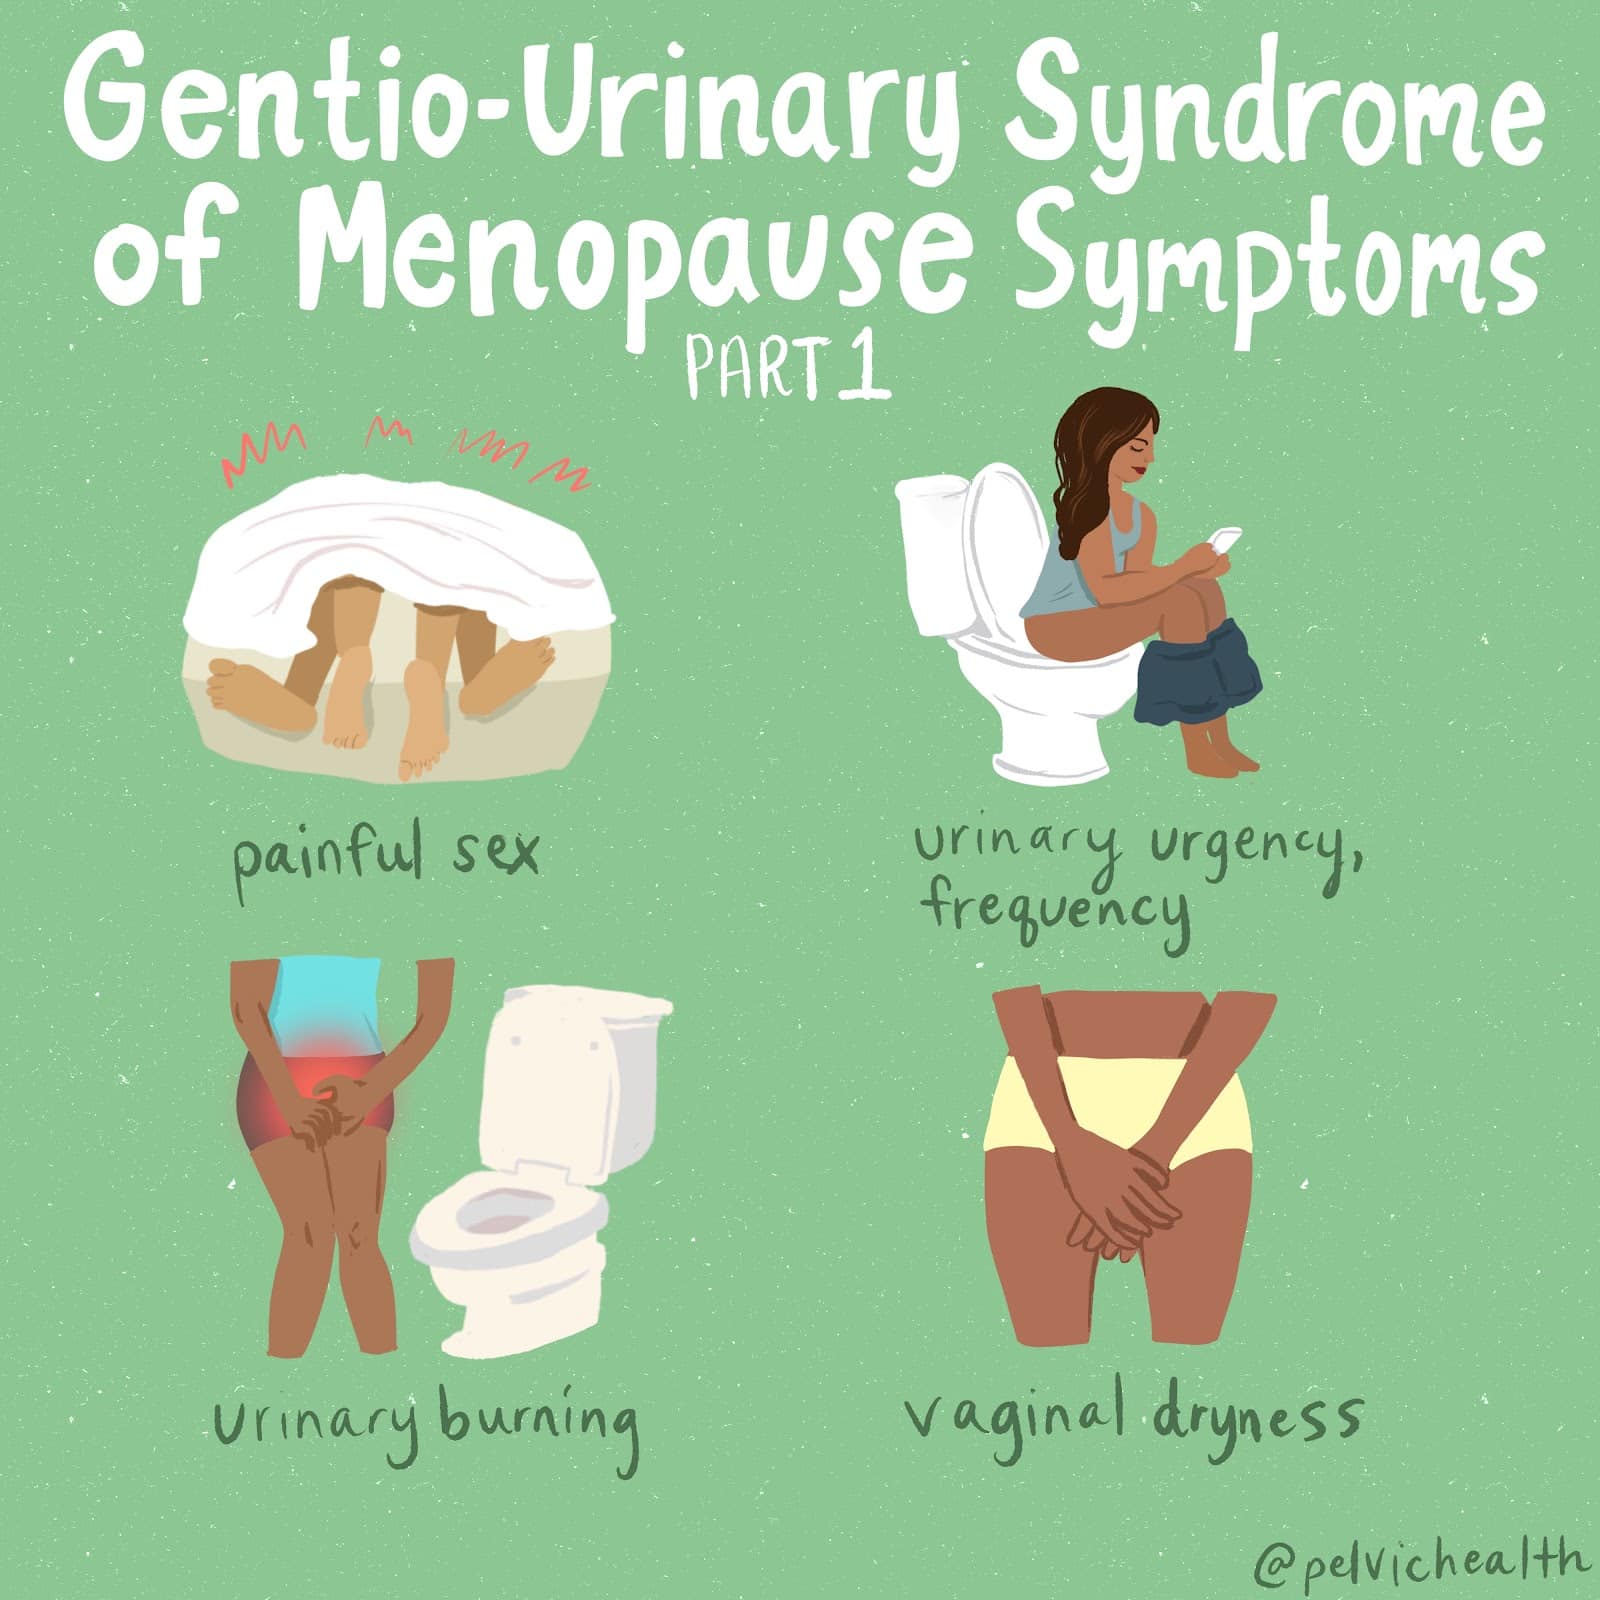

Menopause is more than just hot flushes, night sweats and mood changes! Even though 50% of the population goes through menopause the majority of people and healthcare providers are under-informed about menopause and safe and effective treatments. Too many people are suffering unnecessarily. Perimenopause, the precursor to menopause begins in the 40’s for most people and most women will be in menopause by their early 50’s. Beyond the systemic symptoms of menopause people will start to experience more subtle genitourinary symptoms that will continue to worsen over time if untreated. Painful sex, urinary urgency, frequency, leaking and burning, recurrent vaginal and urinary tract infections and vaginal dryness are symptoms of the Genitourinary Syndrome of Menopause (GSM). The symptoms of GSM are also symptoms of pelvic floor dysfunction, which almost 50% of women suffer by the time they are in their 50s.

Menopause is more than just hot flushes, night sweats and mood changes! Even though 50% of the population goes through menopause the majority of people and healthcare providers are under-informed about menopause and safe and effective treatments. Too many people are suffering unnecessarily. Perimenopause, the precursor to menopause begins in the 40’s for most people and most women will be in menopause by their early 50’s. Beyond the systemic symptoms of menopause people will start to experience more subtle genitourinary symptoms that will continue to worsen over time if untreated. Painful sex, urinary urgency, frequency, leaking and burning, recurrent vaginal and urinary tract infections and vaginal dryness are symptoms of the Genitourinary Syndrome of Menopause (GSM). The symptoms of GSM are also symptoms of pelvic floor dysfunction, which almost 50% of women suffer by the time they are in their 50s.

Symptoms of pelvic floor dysfunction and GSM include:

- Urinary urgency, frequency, burning, nocturia

- Painful sex

- Vulvovaginal pain and burning